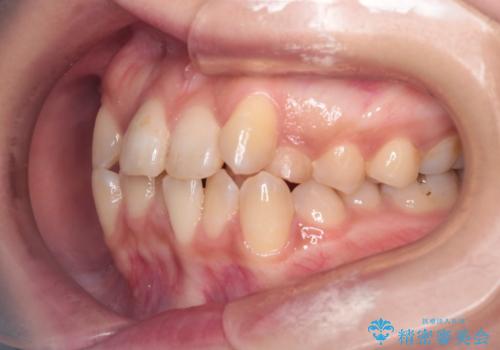

- 患者様は、歯並びのガタガタ(重度の叢生)を改善したいとのことで来院されました。診察すると、歯列のスペース不足が著しく、前歯が重なり合い、噛み合わせにも影響が出ている状態でした。歯をきれいに並べるためには抜歯によるスペース確保が不可欠と判断し、上下の小臼歯4本を抜歯したうえで、目立ちにくい審美ワイヤー矯正(白いワイヤーと透明ブラケット)を用いた治療計画を立てました。

抜歯によって歯を動かすためのスペースを確保。その後、審美ワイヤー矯正を用いて歯を1本ずつ適切な位置に誘導しながら、噛み合わせのバランスも整えていきました。時間はかかりましたが、ガタガタの歯並びがきれいに整い、機能的にも審美的にも満足のいく仕上がりとなりました。患者様からは「歯並びが劇的に改善し、見た目だけでなく噛みやすさも向上した」と喜びの声をいただきました。